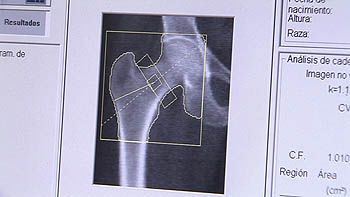

En España hay un promedio anual de 50.000 fracturas de caderas Una de cada dos mujeres, de más de 70 años, puede fracturarse a causa de la osteoporosis